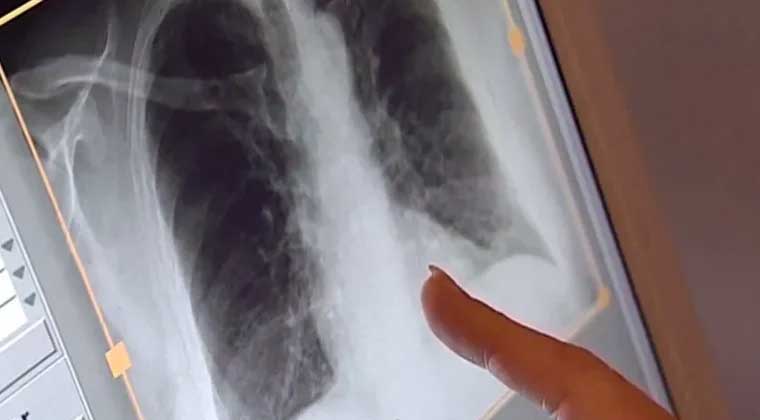

ويُعد السل مرضا معديا يصيب الرئتين بشكل أساسي، وقد تظهر أعراضه بعد أسابيع أو حتى سنوات من العدوى. ورغم إمكانية الشفاء التام عند الالتزام بالعلاج، يحذر الأطباء من أن المرض قد يخلّف آثارا صحية طويلة الأمد، تشمل تلف الرئتين ومشكلات في القلب والتنفس.